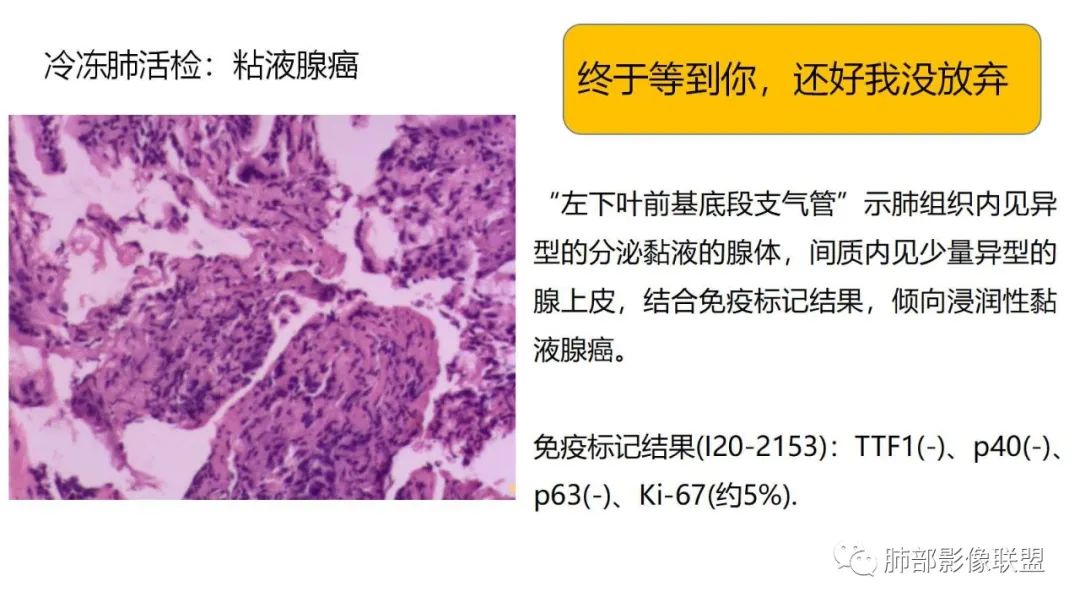

1、患者有咳白色泡沫状黏液痰的病史,患病时间较长。病理阴性不能排除。

三、本例是一个误诊多年的病例,给我们很多启示:

1.多学科探讨的重要性:肾内科忽视肺部病变,后续需要呼吸、影像、病理共同探讨。

2.粘液腺癌易伪装成肺炎的形态,尤其是当患者本身具有免疫色彩的时候,易误诊为间质性肺炎,或肺部感染。若治疗无效,取得病理很重要。

3.粘液腺癌常常因为标本不够,病理无法诊断,影像诊断很重要,取病理方案很重要。甚至多次取病理。